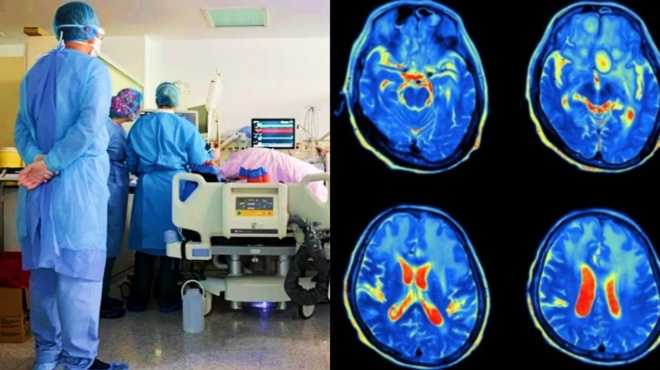

Σύμφωνα με πληροφορίες, το θύμα από το βόρειο Ισραήλ, που δεν είχε υποκείμενα νοσήματα, πέθανε από νεγλαιρίαση – γνωστή επίσης ως πρωτογενής αμοιβαδική μηνιγγοεγκεφαλίτιδα (primary amoebic meningoencephalitis ή PAM) – μια σπάνια λοίμωξη του εγκεφάλου, η οποία προκαλείται από την αμοιβάδα Naegleria fowleri.

Στα πρώτα στάδια της λοίμωξης PAM μέσω της ρινικής κοιλότητας, τα συμπτώματα μπορεί να περιλαμβάνουν έντονο πονοκέφαλο, πυρετό, ναυτία και έμετο. Καθώς η λοίμωξη επιδεινώνεται, τα συμπτώματα – που εμφανίζονται 1-9 ημέρες μετά την έκθεση – μπορεί να εξελιχθούν σε επιληπτικές κρίσεις ή παραισθήσεις.